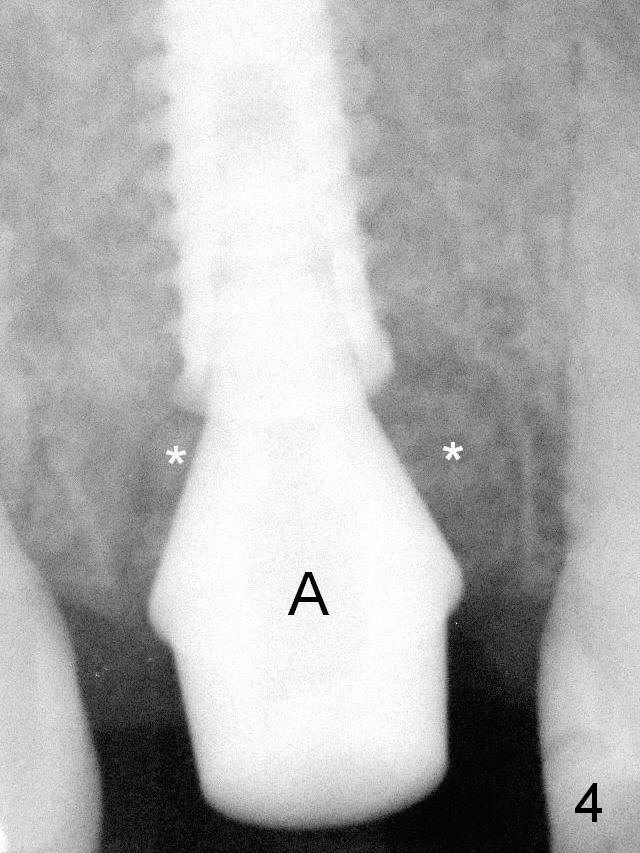

The last drill is 4.3 mm, followed by 4.8 mm Magic Expander since the palatal wall of the osteotomy is thin after the last drill.  A 5x13 mm IBS implant is placed with ~ 45 Ncm.  The apical portion of the 3 sockets is filled with Osteogen plug and the coronal portion with autogenous bone (harvested from MD), mixed with allograft and Osteogen (Fig.4 * as well as collagen plug in the most superficial portion of the sockets).  A 6.5x4(4) mm pair abutment (Fig.4 A) is placed to hold an immediate provisional in place.